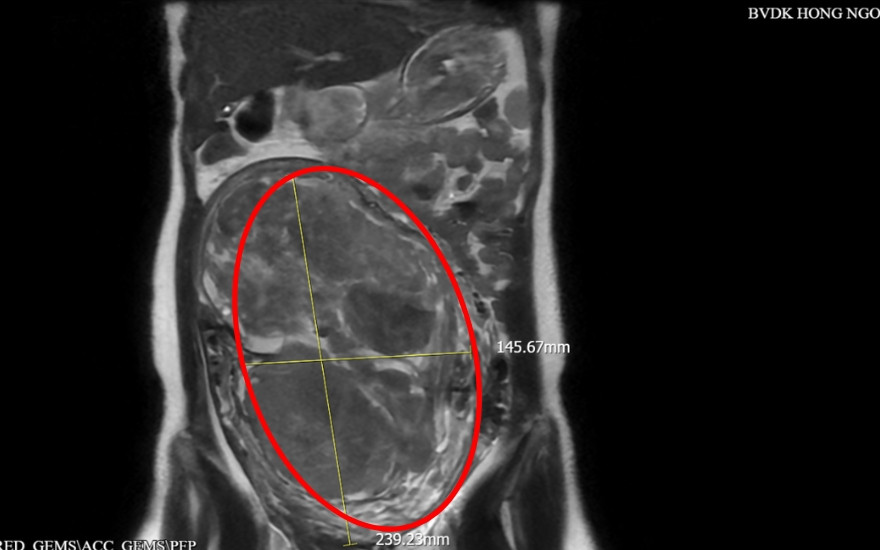

Được người quen giới thiệu, chị tìm đến BVĐK Hồng Ngọc Phúc Trường Minh để thăm khám. Tại đây, kết quả siêu âm và chụp cộng hưởng từ cho thấy khối u choán toàn bộ ổ bụng với kích thước 145x239mm khiến tử cung to bất thường, giải phẫu vùng chậu bị biến đổi đáng kể.

Sau khi hội chẩn chuyên môn, các bác sĩ quyết định lựa chọn mổ mở bóc u xơ thay vì cắt tử cung toàn phần. “Thứ nhất, hình ảnh MRI cho thấy khối u dù lớn nhưng vẫn có ranh giới tương đối rõ với cơ tử cung, chưa xâm lấn lan tỏa toàn bộ thành tử cung. Thứ hai, niêm mạc tử cung vẫn còn được bảo tồn và có thể xác định vị trí bằng siêu âm trong mổ. Điều này mở ra khả năng bóc trọn khối u mà không xâm nhập buồng tử cung, từ đó duy trì chức năng sinh sản”, BS. Nguyễn Văn Xuyên nhận định.